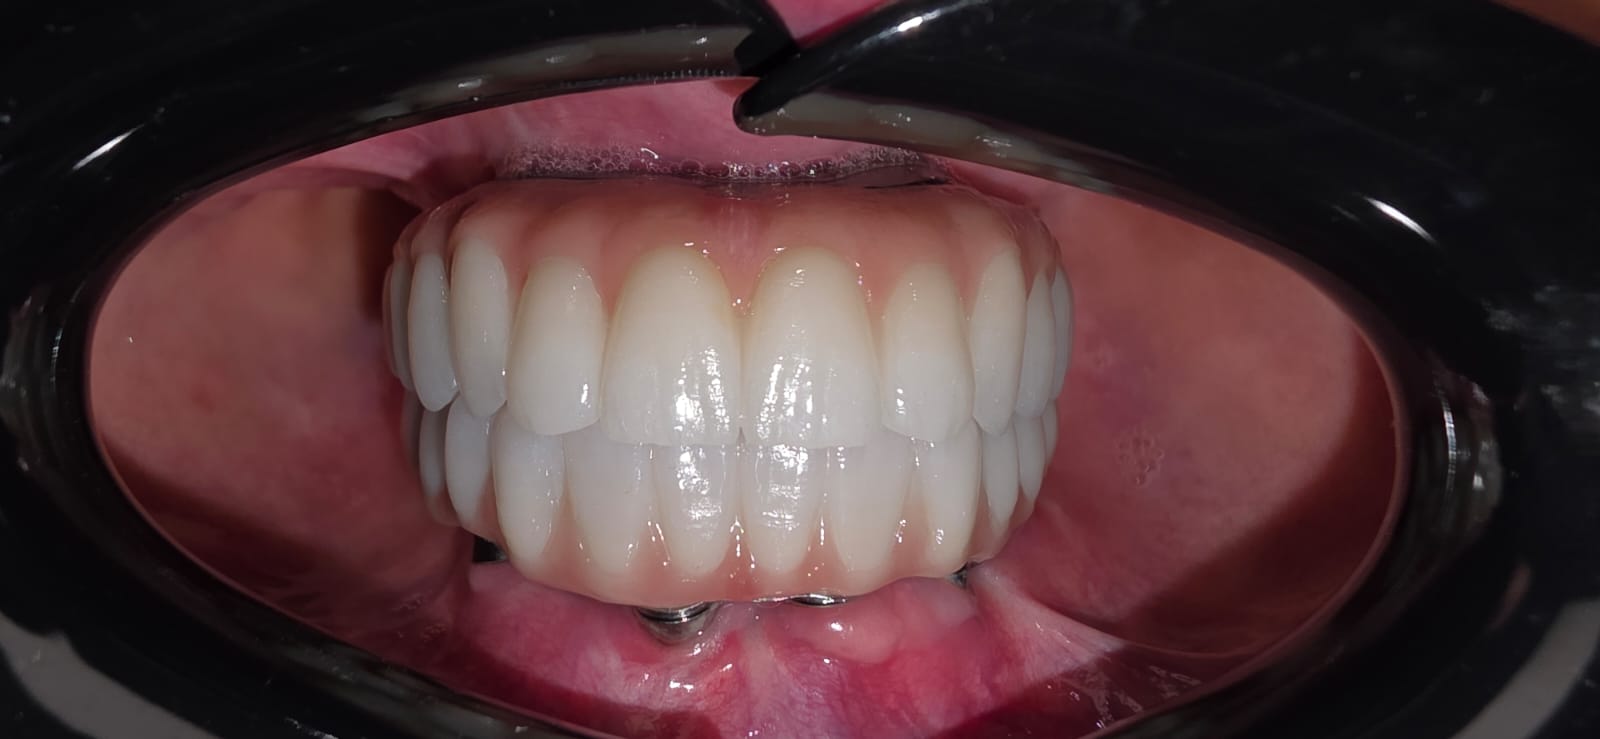

Pas përfundimit të suksesshëm të fazave kirurgjikale, u kalua në vendosjen e punimit definitiv. Trajtimi përfundoi me: 24 kurora zirkoni full anatomi Të mbështetura mbi bar titani Dizajnuara për stabilitet maksimal dhe shpërndarje optimale të forcave Zirkoni u zgjodh për rezistencën e lartë, biokompatibilitetin dhe estetikën natyrale, ndërsa struktura e titanit siguroi qëndrueshmëri afatgjatë të implanteve dhe kurorave.

Rezultati final: më shumë se një buzëqeshje e re

Rezultati përfundimtar ishte shumë më tepër se një transformim estetik.

Pacientja përjetoi:

• Rikthim të plotë të funksionit të përtypjes

• Stabilitet absolut gjatë të folurit dhe ushqyerjes

• Eliminim të ndjesisë së kalimit të ajrit

• Rritje të ndjeshme të vetëbesimit dhe cilësisë së jetës